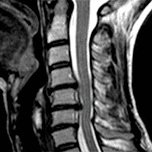

Síndrome de Arnold Chiari I,

Escoliose e Siringomielia idiopáticas.